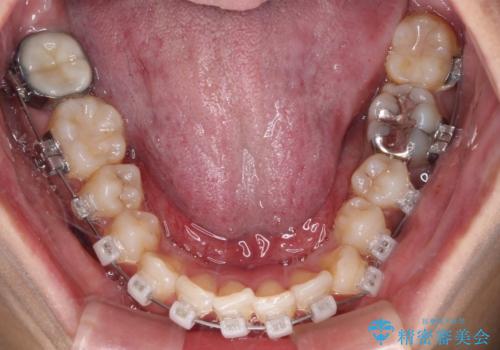

- クリアブラケット

- 2年1ヶ月

- 10-30回

片側での抜歯であると、正中が抜歯した方向にずれていくため、左上の奥歯を遠心移動させる目的でアンカースクリューと補助装置を併用した上で、ワイヤー装置にて矯正治療を行うこととしました。